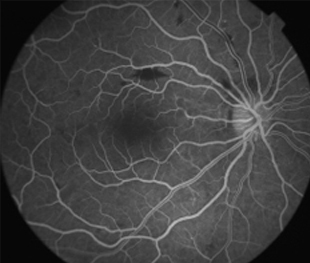

2 meses: disminución de manchas algodonosas y hemorragias con mejoría de circulación

- Angiografía: teñido arterial, escape capilar, más tardíamente, no perfusion arteriolar y venular con teñido de las paredes vasculares y dilatación venosa.